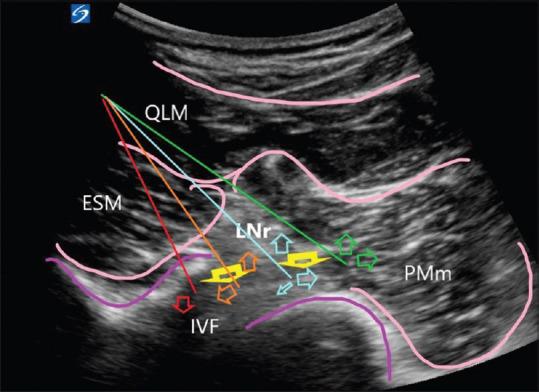

The outcomes of plexus and peripheral nerve blocks depend on needle-nerve contact and the spread of local anesthetic (LA) around the plexus or nerve. Needle-nerve distance and spread of LA could be visualized during US-guided lumbar plexus block (LPB).

In all 24 patients, we observed an oval and antegrade LA spread after lumbar plexus was identified with neurostimulation at L3. With the needle closer to intervertebral foramina (IVF), a retrograde spread was visualized. Only 2/24 patients received rescue analgesia in the first 24 h.

在所有24例患者中,在L3处通过神经刺激确定腰丛后,我们观察到LA呈椭圆形且向前扩散。当针靠近椎间孔(IVF)时,可观察到逆行扩散。仅2/24例患者在最初24小时内接受了补救镇痛。